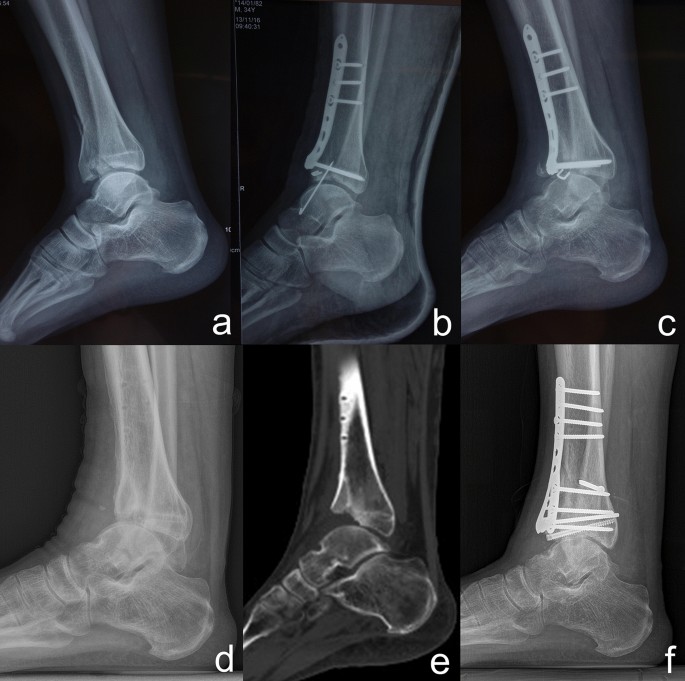

Temporary Stabilization Methods

While soft tissues heal, stabilization may include:

-

Splints or casts

External fixation devices applied surgically

An external fixator holds the bones steady above and below the fracture while avoiding damaged skin and soft tissue. This allows swelling to decrease while maintaining alignment and monitoring healing.

Treatment Options After Swelling Improves

Once soft tissues are ready, several treatment approaches may be used depending on fracture severity.

Limited Internal Fixation

Uses small incisions to secure key fracture fragments. This method reduces soft tissue disruption and is often combined with casting or external fixation.

Internal Fixation

Plates and screws are used to restore bone alignment more precisely. Even with excellent alignment, ankle arthritis remains a common long-term complication.